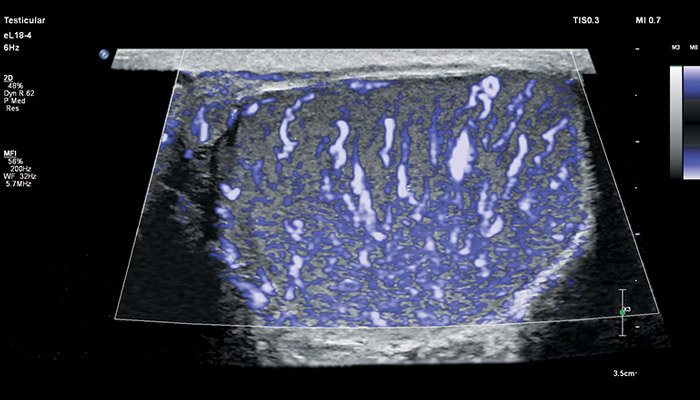

Бесспорное достоинство датчика – его универсальность. УЗ-аппараты, оснащённые eL18-4, помимо акушерства можно использовать для обследования щитовидной железы, молочных желёз, сосудов шеи, рук и ног, органов мужской репродуктивной системы, брюшной полости и малого таза детей и подростков.

Сочетание усовершенствованной технологии PureWave, комплексного решения по эластографии, высокочувствительной визуализации кровотока (MicroFlow) и точной биопсии представляет собой эффективное решение для ультразвуковой оценки мелких образований.

Линейный матричный датчик eL18-4 поддерживает режим высокочувствительной визуализации кровотока (Philips MicroFlow Imaging), новый запатентованный метод, который обеспечивает инновационный подход к оценке сосудистого русла. Визуализация MicroFlow преодолевает многие барьеры, связанные с традиционными методами обнаружения кровотока в малых сосудах, обеспечивая высокое разрешение при минимальных артефактах. Метод MicroFlow Imaging поддерживает высокую частоту кадров и качество изображения, применяет инновационные методы сокращения артефактов. Варианты вычитания 2D-изображений, смешивания и параллельного отображения обеспечивают превосходную визуализацию в различных клинических случаях.